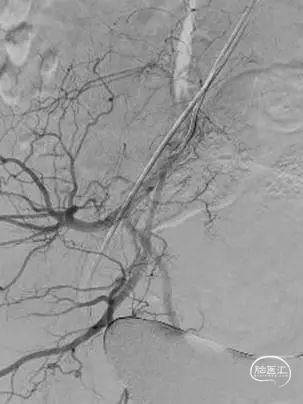

2.0×9mm球囊扩张,可见残余狭窄较重。

二次球囊扩张后可见狭窄明显改善,血流速度增快。

植入3.5×15自膨支架。

工作角度造影示:支架完全打开,贴壁良好。